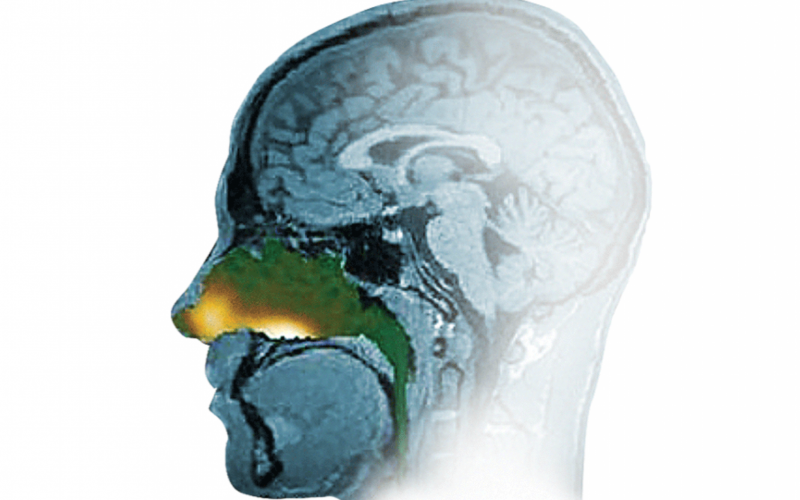

XHANCE (fluticasone propionate) nasal spray is a drug-device combination product that combines the most widely used nasal anti-inflammatory drug with the innovative Exhalation Delivery System.

Photo Via Company